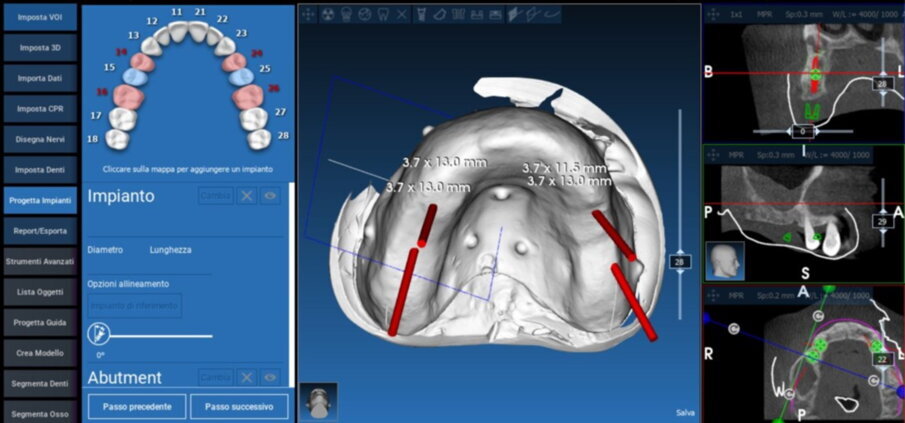

Il software consente di visualizzare sezioni assiali, coronali, sagittali, trasversali nonché ricostruzioni panorex e 3D (rendering), e di ottenere la sovrapposizione dei dati DICOM con i file STL, ottenuti mediante scansioni ottiche, intra o extraorali. Questi software permettono di selezionare i siti più adatti, la forma e la lunghezza di ciascun impianto, e permettono di prevedere la necessità e la quantità di un eventuale innesto osseo

(Figg. 17-18).

Figg. 19, 20_Progettazione Cad con software Realguide.